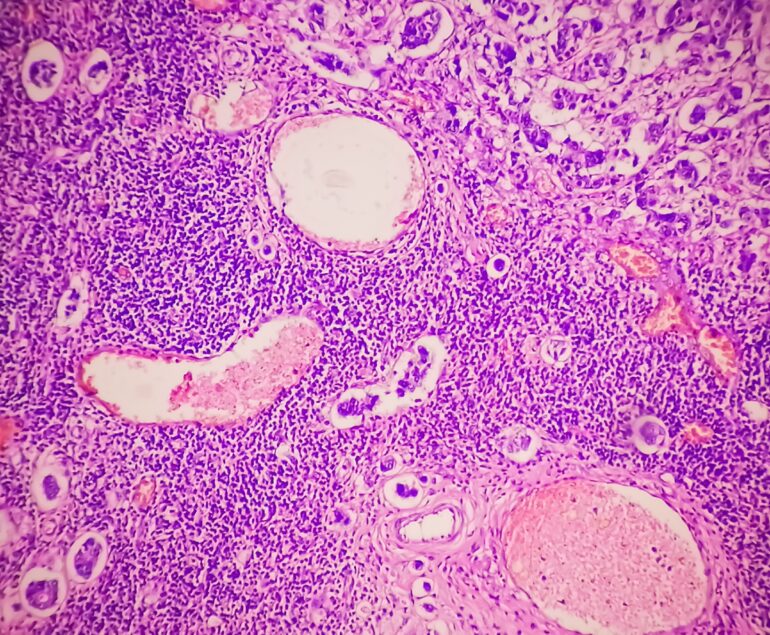

Pathology with Accessible Expertise

Diagnostic Excellence

Our team of expert pathologists, trained at leading institutions, is dedicated to providing top-tier, accurate…

Board Certified Pathologists & Experts in a Variety of Subspecialty Areas